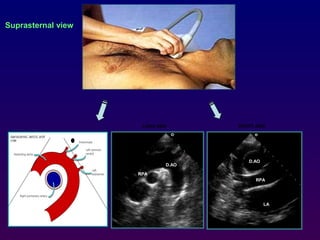

Suprasternal view

With the patient supine and the neck extended, the

transducer is placed in the suprasternal notch to

obtain a long-axis image of the distal ascending,

transverse, and proximal descending aorta.

The take- off of the left carotid and left subclavian

artery may also be appreciated. Centrally positioned

and "beneath" the aortic arch is a short-axis of the

right pulmonary artery This view may be particularly

valuable for the evaluation of suspected patent

ductus arteriosus, aortic coarctation, or aortic

dissection.

AV

A.AO

RPA

D.AO

LONG AXIS SHORT AXIS

LA